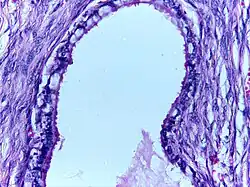

Mucinous cystadenoma | Micrograph showing Mucinous Cystadenoma of ovary. The cyst wall is lined by tall columnar epithelium and filled with mucin. | Category: Histopathology of mucinous cystadenoma | Mucinous cystadenoma |

![]() |